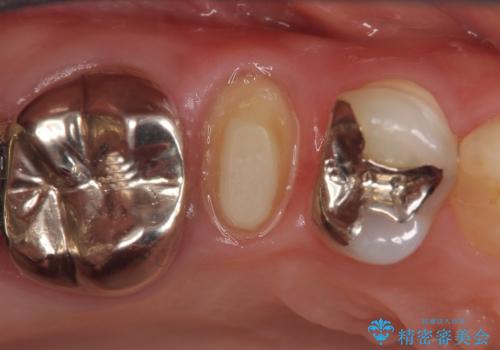

- 右上5番目の歯がなにもしなくてもズキズキ痛むので診て欲しいといらっしゃった方の症例です。

診査の結果神経を保存するのは困難だったため、根管治療を行った後、オールセラミッククラウンによる補綴を行いました。

今回用いたオールセラミッククラウンはジルコニアフレームという白い素材の上にセラミックを盛っているため、審美性が非常に高いのが特徴です。